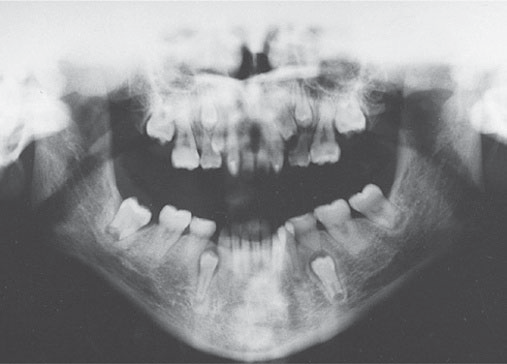

Hình 5.4: Hình ảnh phim toàn cảnh (orthopantomogram) của một bé trai 16 tuổi mắc hội chứng loạn sản xương đòn sọ (cleidocranial dysplasia). Chú ý sự hiện diện của nhiều răng vĩnh viễn dư và tình trạng ngừng mọc của nhiều răng vĩnh viễn bình thường.

Hình 5.5: Hình ảnh phim toàn cảnh (orthopantomogram) của một bé gái 13 tuổi mắc hội chứng tóc-răng-xương (tricho-dento-osseous syndrome). Chú ý tình trạng mọc răng vĩnh viễn chậm nghiêm trọng ở nhiều răng và xương hàm có mật độ dày đặc

Hình 5.6: Hình ảnh phim toàn cảnh (orthopantomogram) của một bé trai 10 tuổi mắc hội chứng xương dày (pycnodysostosis). Chú ý tình trạng mọc chậm của nhiều răng vĩnh viễn và xương hóa đá (osteopetrotic bones).